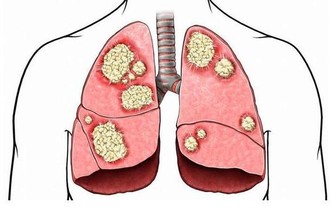

吃完雞蛋後吃柿子輕則會得食物中毒,總則會導致急性腸胃炎還有肺結石。一般而言,這兩種食物同時吃會導致以上吐、下瀉、腹痛為主的急性胃腸炎癥狀。所以如果服用時間在1~2小時內,可使用催吐的方法。立即取食鹽20g加開水200ml溶化,冷卻後一次喝下,如果不吐,可多喝幾次,迅速促進嘔吐。或者可用鮮生薑搗碎取汁用溫水沖服。如果服用時間較長,儘快服用些瀉藥將有毒物質排除體內。